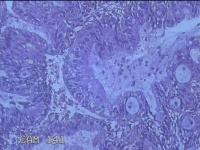

宫颈赘生物

性别

女

年龄

41岁

临床诊断

1.稽留流产 2.慢性宫颈炎

一般病史

停经2个月,阴道流血5天。

标本名称

大体所见

灰白粉红色肿物1.5x0.7x0.3cm一个,表面光滑。

息肉,上皮呈分泌反应